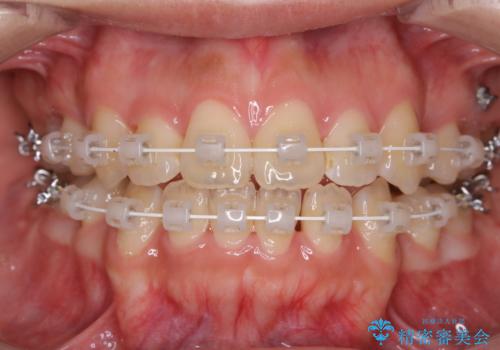

ワイヤー矯正中のクリーニング

担当医 歯科衛生士